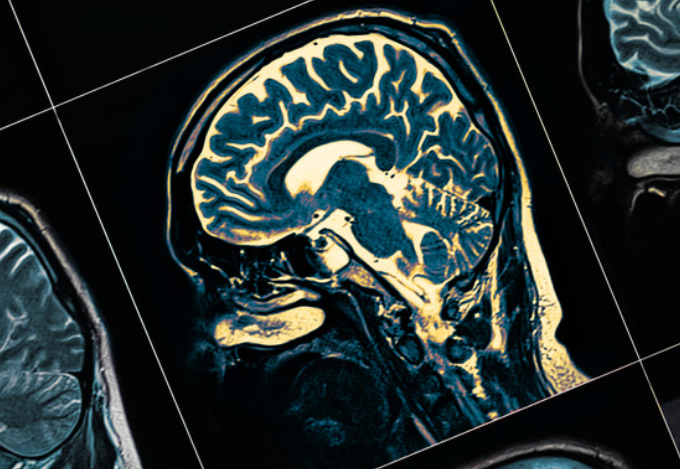

파킨슨 병은 뇌의 일부 영역이 손상됨으로써 발생하는 질환입니다.

파킨슨병은 뇌 신경학적 질병이기 때문에 정신건강에 위험이 되는 우울증과 같은 증상을 동반하기도 합니다.